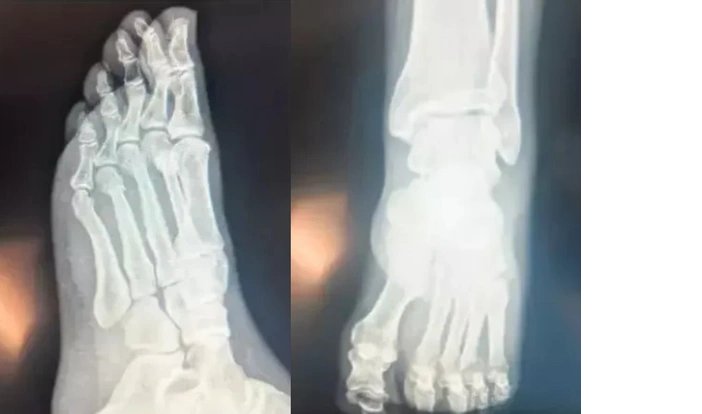

CHP Genel Başkanı Özgür Özel’in “Herkes inceleyebilir” dediği filmleri inceleyen Ortopedist Prof .Dr. Tarık Yazar, şu değerlendirmeleri yaptı:

“Sayın Özgür Özel’in röntgen filmlerini incelediğimizde parmak kemiklerindeki kırıkları gördüm. Açık bir yara olmaması bir şanstır. Yani, dışarıya kan akmamış. Röntgende yara olup olmadığı her zaman görülmez. Ancak, Özgür Bey’in röntgenini incelediğimizde yine de şanslı olduğunu gördüm. Biz buna ‘şanslı kırık’ deriz. Aslında tam kırık da diyemeyiz. Ayrılmamış, kemiğin özelliği bozulmamış. İyileşme yeteneğinin fazla olduğu bir bölgede kırık var. Şanslı tarafı kanlanmanın kuvvetli olduğu bir bölgede kırık gördüm. Bilgisayarlı tomografiyle takibi uygun olur. Tedaviye doğru başlanmış. Mutlaka iyileşecektir. Kullandığı ayak desteği gayet doğru bir seçim. Üç aya kalmaz tam iyileşme gerçekleşir. Lütfen bir daha düşmesin"